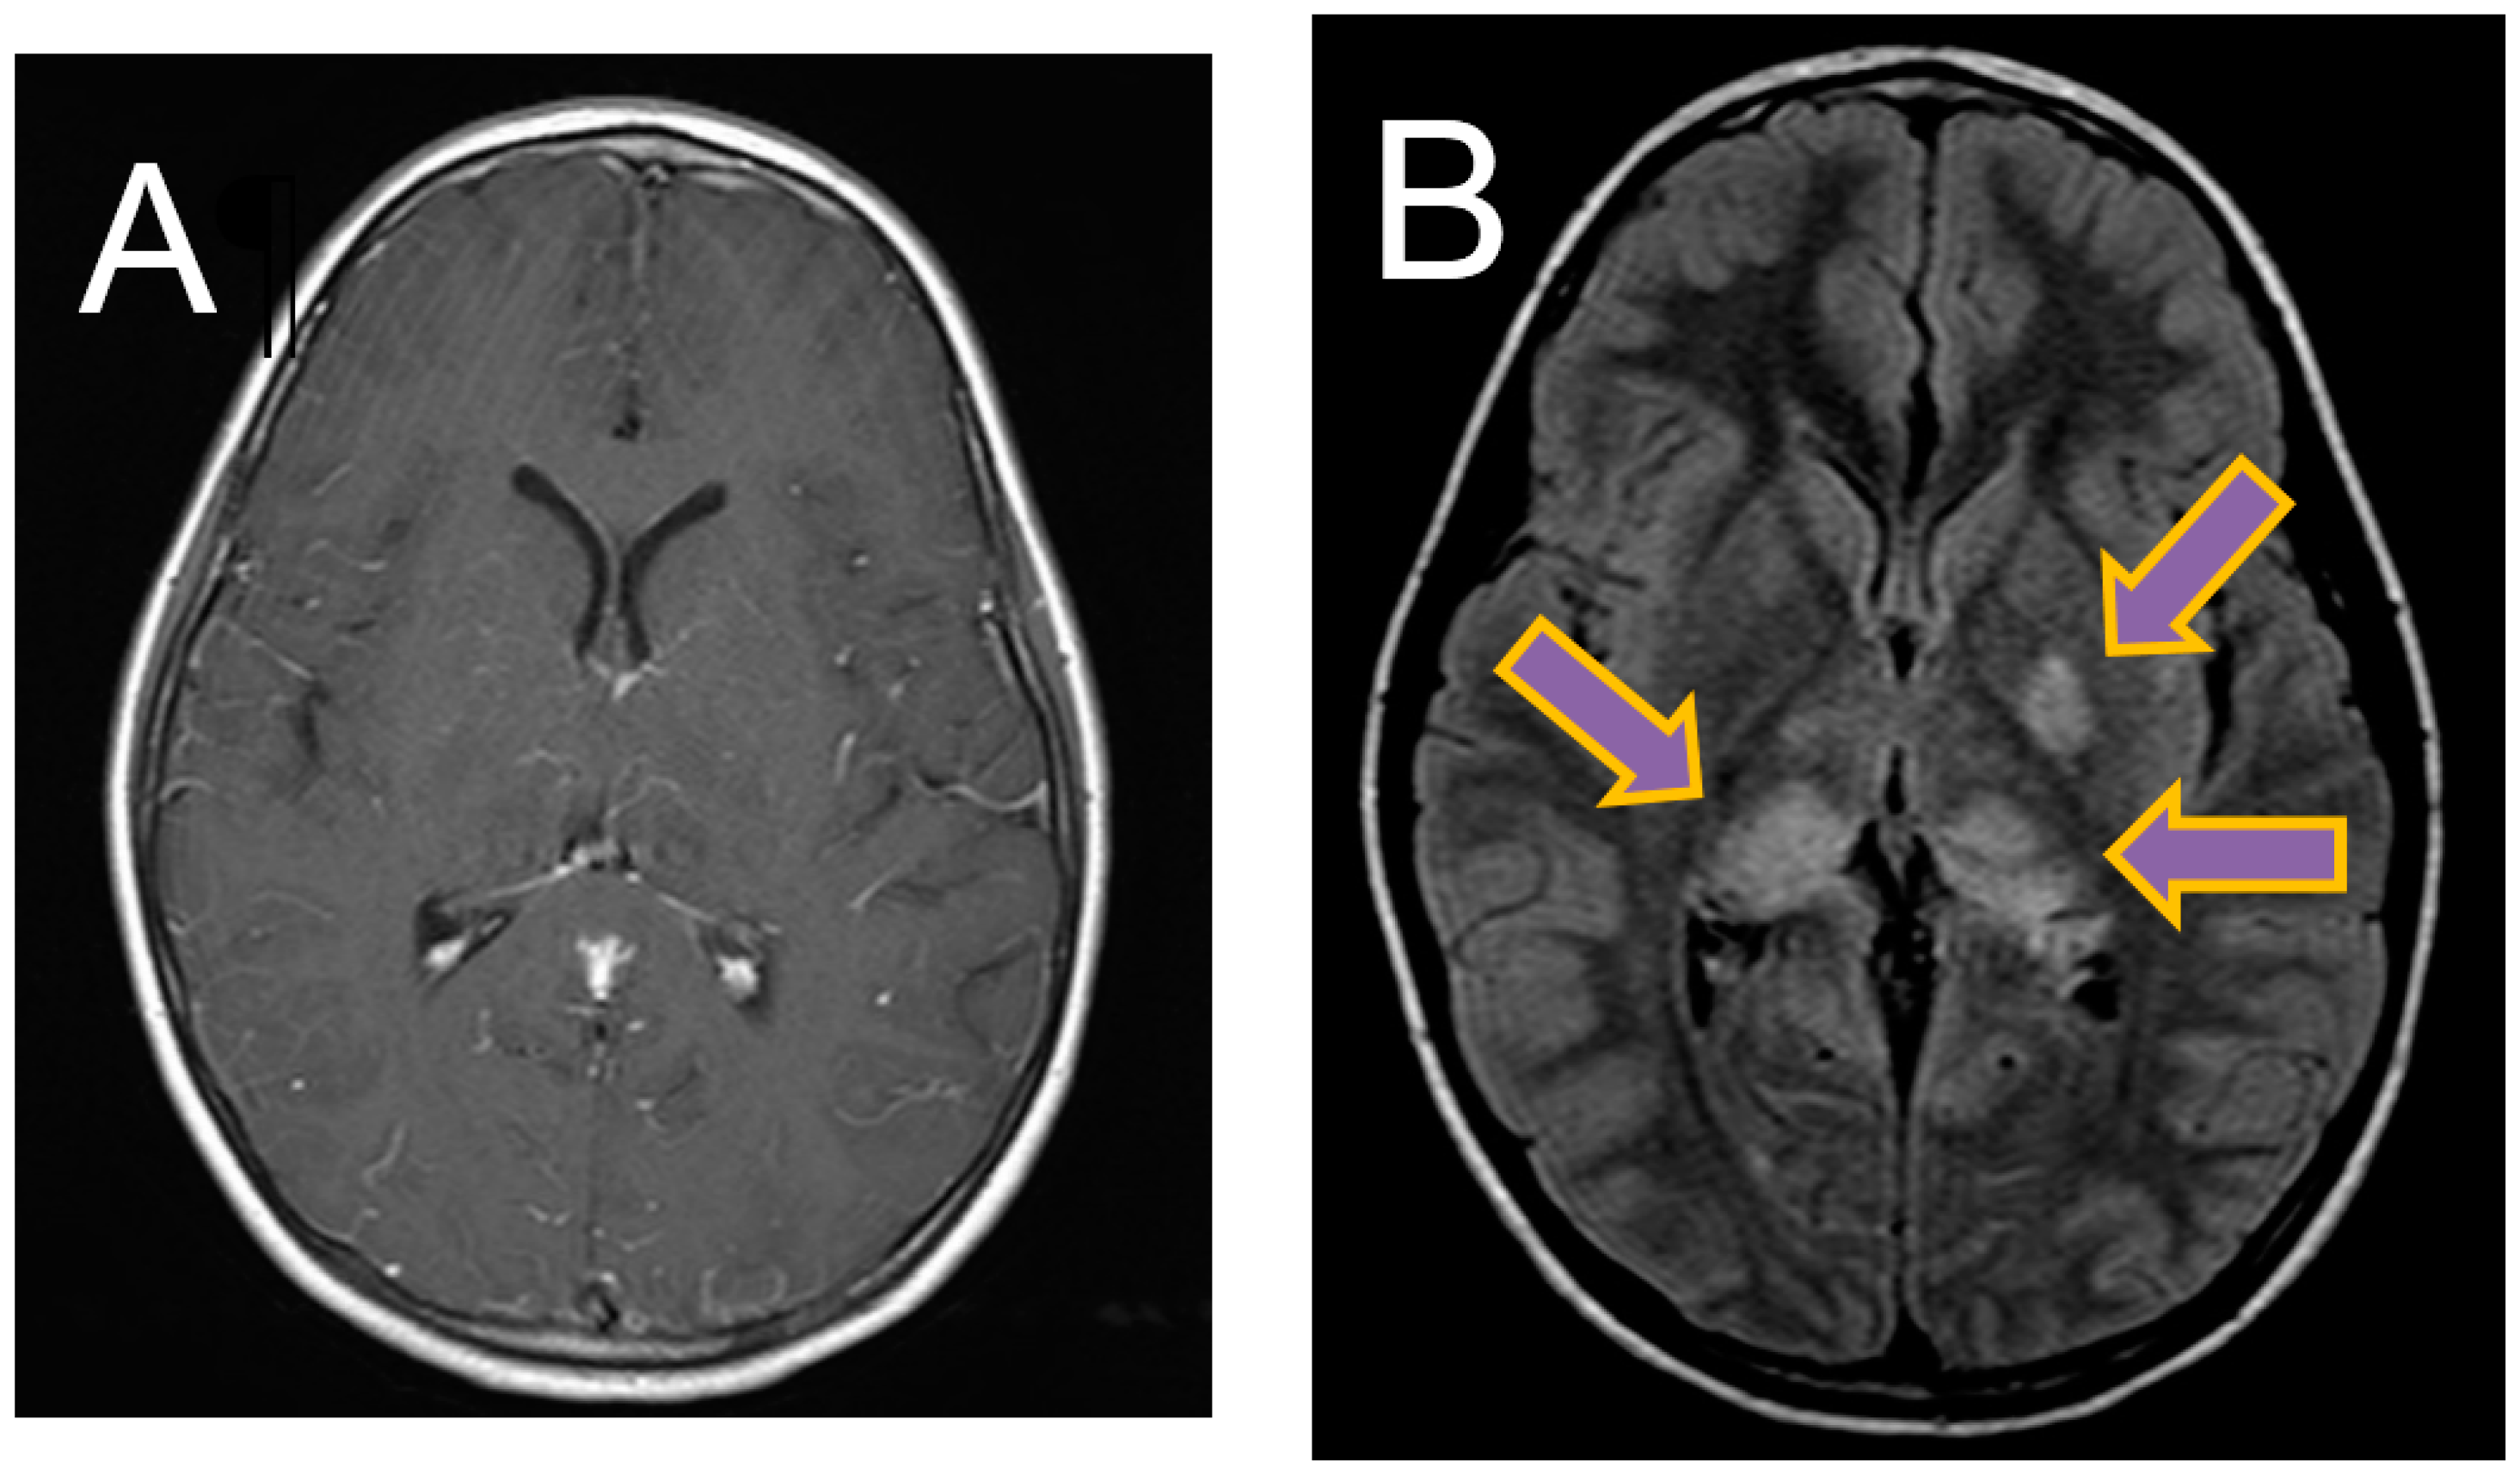

A lumbar puncture was performed and revealed a cerebrospinal fluid (CSF) leucocytosis (388 × 106/L) with 80% polymorphonuclear cells, an elevated CSF protein of 0.86 g/L (NR 0.15–0.45 g/L), and CSF glucose of 2.7 mmol/L (NR 2.7–4.2 mmol/L). Magnetic resonance imaging (MRI) of the brain revealed diffuse leptomeningeal enhancement with T2 and FLAIR hyperintensity and restricted diffusion involving the left basal ganglia and bilateral thalami (Figure 1).

Figure 1. Magnetic resonance imaging (MRI) brain images. (A) Axial T1-weighted image showing diffuse leptomeningeal enhancement. (B) Axial FLAIR image showing FLAIR hyperintensity in left basal ganglia and bilateral thalami.